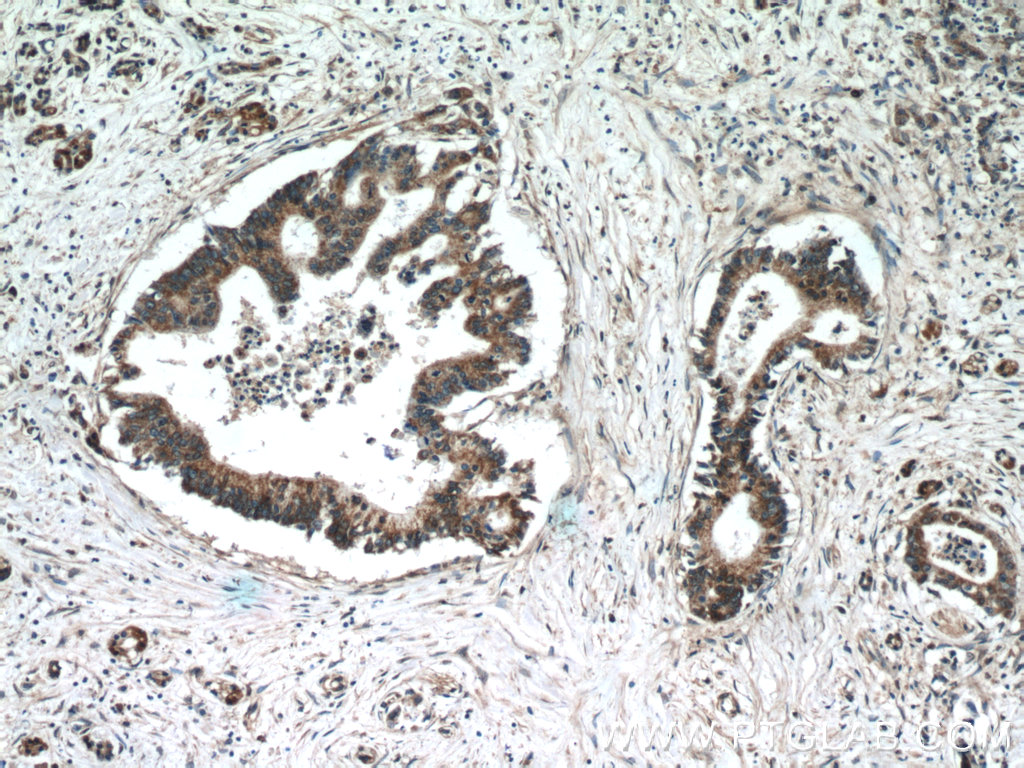

| Positive IHC detected in | human pancreas cancer tissue Note: suggested antigen retrieval with TE buffer pH 9.0; (*) Alternatively, antigen retrieval may be performed with citrate buffer pH 6.0 |

| Immunohistochemistry (IHC) | IHC : 1:20-1:200 |